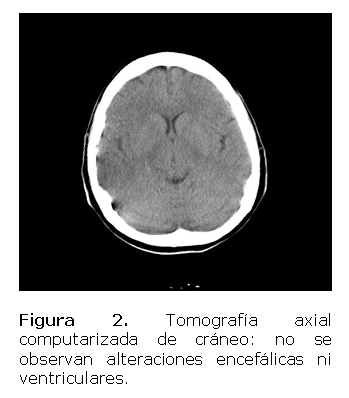

Con estos resultados se remite a la consulta de Neumología y Neurología con la sospecha diagnóstica de cáncer de pulmón, donde le realizan tomografía cerebral (Figura 2) no observándose alteraciones encefálicas ni ventriculares que explicaran las manifestaciones neurológicas.